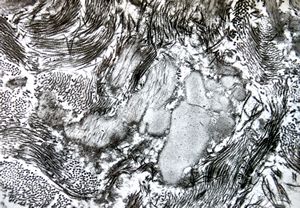

F,68y. | xanthomatous cell in atherosclerotic plaque - a. vertebralis